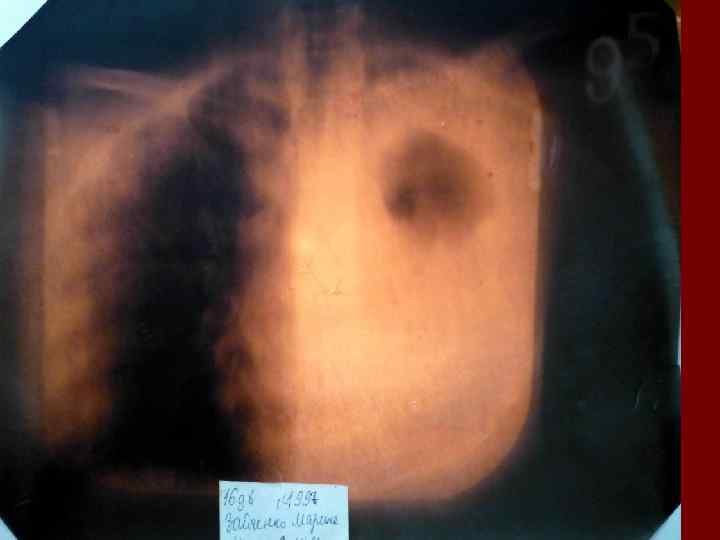

Долевая пневмония характеризуется лобарным пневмоническим инфильтратом. Крупозная ( пневмококковая) пневмония диагностируется прежде всего по клиническим данным. Крупозная пневмония сохраняет свою типичную картину пневмококковой пневмонии: острое начало с характерными клиническими данными, циклическое течение, несклонность к деструкции, гомогенной и лобарной инфильтративной тенью при рентгенологическом исследовании. Вместе с тем, широкое использование антибиотиков способствовало значительному снижению числа крупозных пневмоний у детей. Интерстициальная – редкая форма пневмоний, при которой оказывается поражен прежде всего интерстиций. Как правило, интерстициальная пневмония обусловлена вирусами, пневмоцистами, внутриклеточными микроорганизмами и грибами.

Морфологическую форму пневмонии определяют по клинико – рентгенологическим данным: выделяют очаговую, очагово – сливную, долевую ( крупозную), сегментарную и интерстициальную пневмонии. Очаговая – наиболее распространенная форма. Пневмонические очаги чаще бывают размером 1 см и более. Очагово – сливная – инфильтративные изменения в нескольких сегментах или во всей доле легкого, на фоне которых могут быть видны более плотные участки инфильтрации и/или полости деструкции. Сегментарная – в процесс вовлекается весь сегмент, который, как правило, находится в состоянии гиповентиляции, ателектаза. Морфологическая картина воспаления при очаговых и сегментарных пневмониях связана с первичным инфекционным воспалением в бронхах, что дает основание отнести эти варианты поражения легочной ткани к бронхопневмониям, нередко сопровождающихся бронхообструктивным или бронхообтурационным синдромами. В настоящее время данный тип пневмоний у детей встречается наиболее часто.